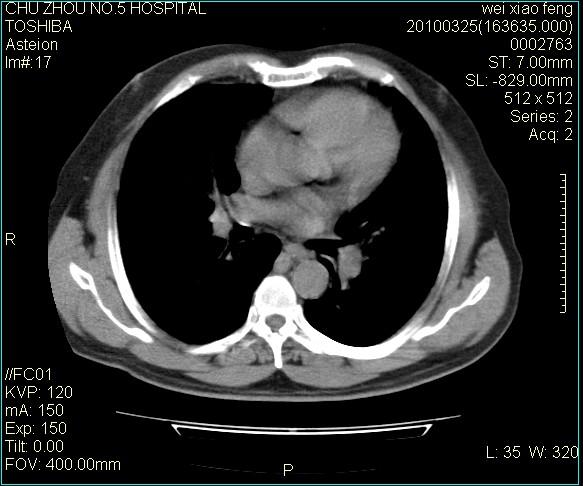

男,60岁,反复咳、痰、喘3月,加重3天。

双肺间质性改变。

考虑双肺血型潘散肺结核/

间质性肺炎伴间质纤维化!不排除伴有职业病!

急性血型潘散肺结核。

双肺间质纤维化,双肺血型潘散肺结核。

心功能怎么样?感觉象肺淤血。

考虑间质性肺炎伴间质纤维化。

肺泡癌不除外

右肺中叶结节影为原发灶,考虑右肺中叶周围型肺癌并淋巴道转移